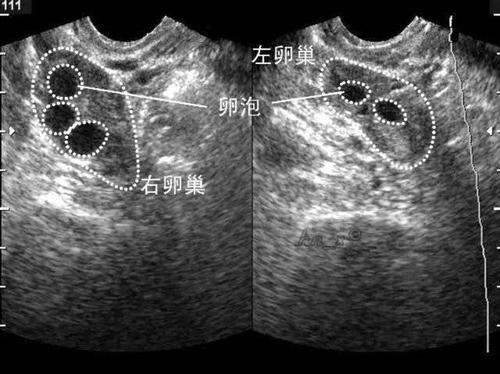

阴道B型超声动态监测卵泡的发育及排卵,是监测排卵最准确可靠的方法。通过阴道B超检查可以了解子宫及双侧附件(卵巢和输卵管)区的基本情况,测定卵巢内的窦卵泡计数,评估卵巢储备功能,动态监测排卵。

排卵监测